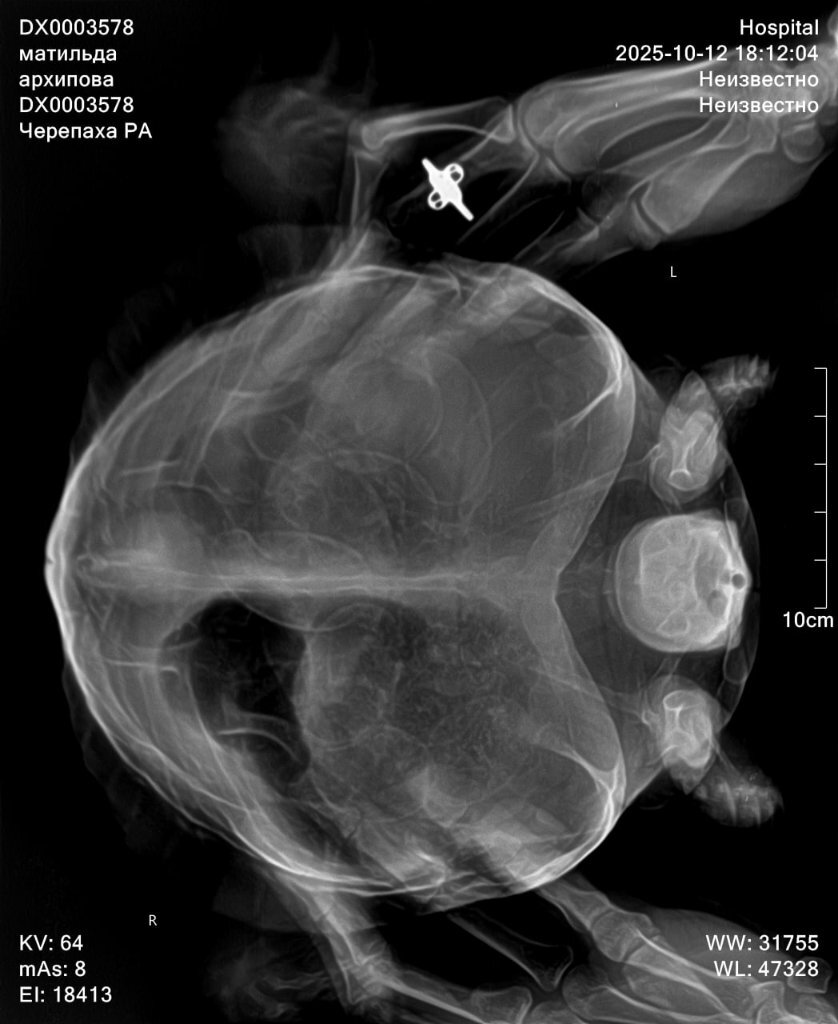

Здраствуйте, сегодня обратилась в другую клинику, прогноз не благоприятный, есть признаки почечной недостаточность, есть переизбыток бактерий в кале, есть признаки стоматита в полости рта. Все это очень и очень плохо. Сделали рентген по направлению, к сожалению описание рентгена рентгенологи сделать не могут, без дополнительной платы. Но завтра я уже записана со снимками на повторный приём. Моя огромная ошибка что ограничилась визитами к одному доктору, и потеряла очень много времени. Тк изначально состояние более стабильное хотябы визуально. Завтра получим назначения от главного врача специалиста по экзотам. Покажу им новые снимки. По фото вроде насчитала тоже количество яиц. Но они значительно сместились, вероятно из-за не к месту сделанного окситоцина